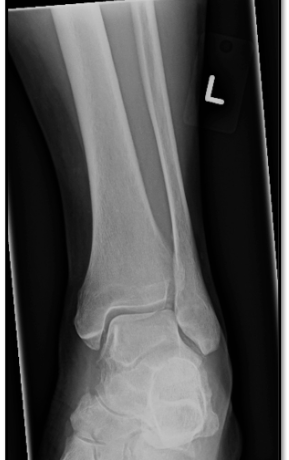

Q

error

A

internal rotation